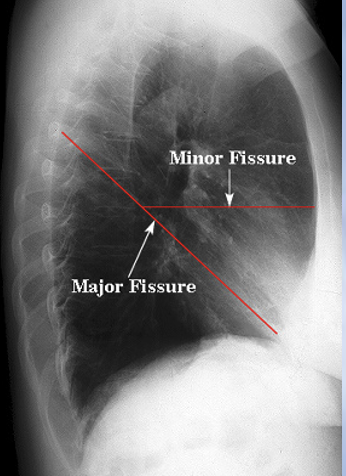

Q

Which right lung fissure is oriented obliquely?

A

Major Fissure

22

The minor fissue separates which right lung lobes?

The RUL and RML